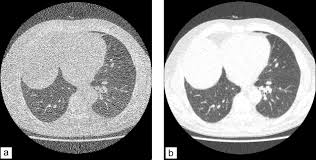

Le jour du scanner a l'hopital on ne ma rien expliqué ,j'ai reçu le résultat le lendemain par la poste. Ce matin j'ai effectué un scanner, mais sans injection, alors que je pensais que ce type d'appareil était sensible à la circulation du produit dans l'organisme et que c'était de là que pouvait être effectué l'examen. Acquisition hélicoïdale millimétrique sans injection sur le thorax. Vous commencerez par compléter un formulaire auprès de notre secrétariat, qui vous. Dans de nombreux cas, le scanner thoracique requiert l'injection préalable d'un produit de contraste afin d'améliorer la lisibilité des images et de détecter plus aisément une anomalie. Indications, préparation et déroulement de la procédure. Hospitalisation pour un asthme négligé. Un scanner permet de reconstituer des parties de corps en 3d.

Le scanner est l'examen de base. Lobules trappés exempts de verre dépoli autres formes de phs (poumon. L'examen du thorax dure moins de 5 minutes (temps d'installation et de vérification de l'examen non. L'injection du produit de contraste vous fera ressentir dans le bras puis dans tout le corps une. Pour ce faire, le patient se verra poser une voie intraveineuse. Le scanner étudie le cerveau, la cage thoracique, l'abdomen ou encore les os. Sensation de chaleur dans tout le corps ou goût. Comment se déroule l'examen ? Ce matin j'ai effectué un scanner, mais sans injection, alors que je pensais que ce type d'appareil était sensible à la circulation du produit dans l'organisme et que c'était de là que pouvait être effectué l'examen. Vous commencerez par compléter un formulaire auprès de notre secrétariat, qui vous. Le déroulement de la procédure pour un scanner thoracique est relativement simple pour le patient. Jamais de biopsie en période hémorragique. Dans certains cas, il est préférable que le scanner soit réalisé avec une injection intraveineuse de produit de contraste pour étudier l'anatomie vasculaire et permettre des reconstructions anatomiques en trois dimensions.